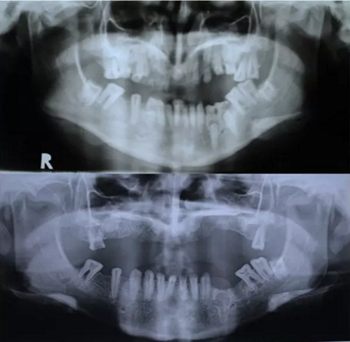

圖 2. 曲面斷層片(術(shù)前、拔牙后、種牙后)

圖 3. 側(cè)位片(術(shù)前及牽張前)